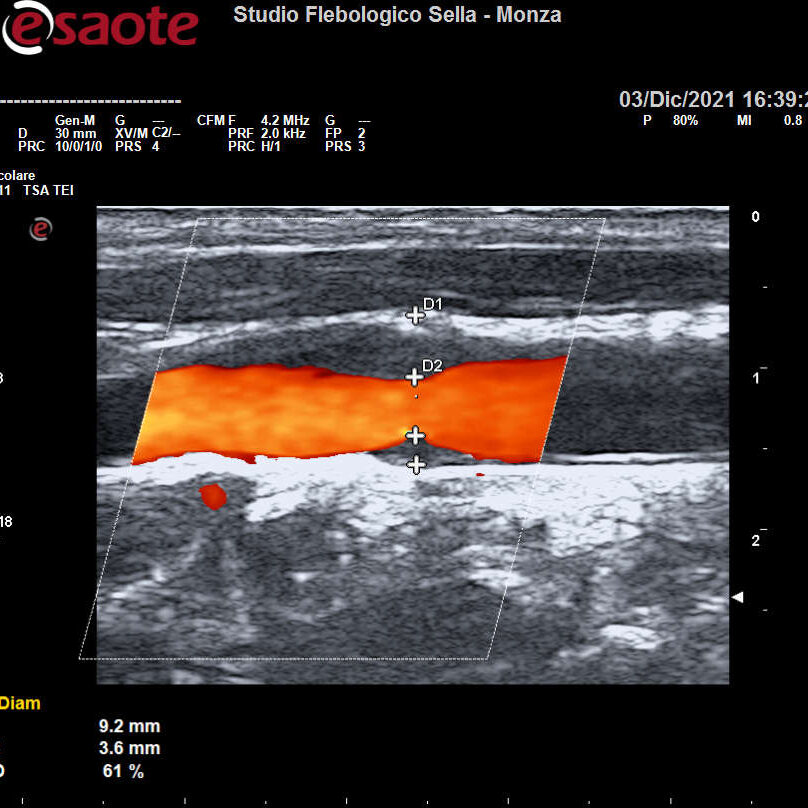

Abbiamo precedentemente visto come l’intuizione del fisico austriaco Christian Doppler ha posto le basi teoriche per la nascita dell’EcocolorDoppler. La deformazione degli ultrasuoni nell’attraversare il corpo umano consente la ricostruzione in immagini dei tessuti, vasi compresi. Otteniamo quindi informazioni sulla forma e il decorso dei distretti vascolari esplorati e sulla velocità del sangue contenuto. Un utile campo applicativo è rappresentato dall’EcocolorDoppler dei tronchi sovraortici ossia lo studio delle arterie del collo. Il precoce riscontro di problemi a carico di carotidi e vertebrali ne previene infatti una grave complicanza: l’ictus ischemico.